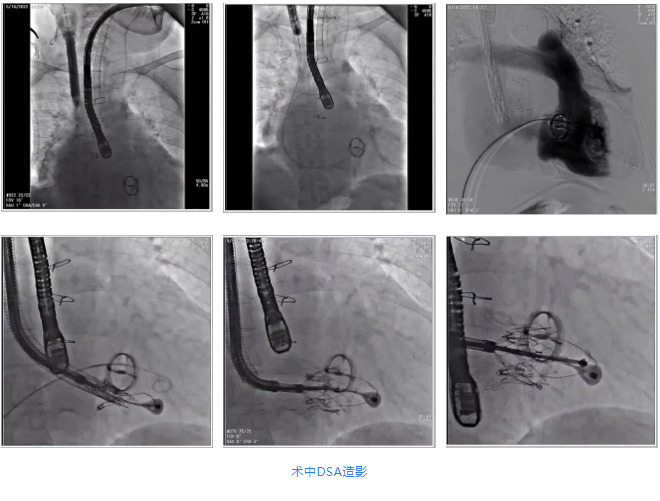

根據(jù)術(shù)前評估結(jié)果,郭應(yīng)強教授團(tuán)隊為患者量身定制了手術(shù)策略,決定使用LuX-Valve Plus經(jīng)血管三尖瓣置換系統(tǒng)開展手術(shù)治療。手術(shù)在全麻下進(jìn)行,采用經(jīng)右側(cè)頸靜脈入路,在經(jīng)食道超聲和DSA的指引下調(diào)整輸送器角度以達(dá)到正確位置,勾住前瓣后逐步釋放盤片,盤片打開后順利扎針,最終完成瓣膜植入,輸送器撤出。術(shù)后超聲提示人工三尖瓣同軸性良好,瓣架固定牢靠,無反流和瓣周漏,術(shù)后三尖瓣平均跨瓣壓差為1 mmHg。